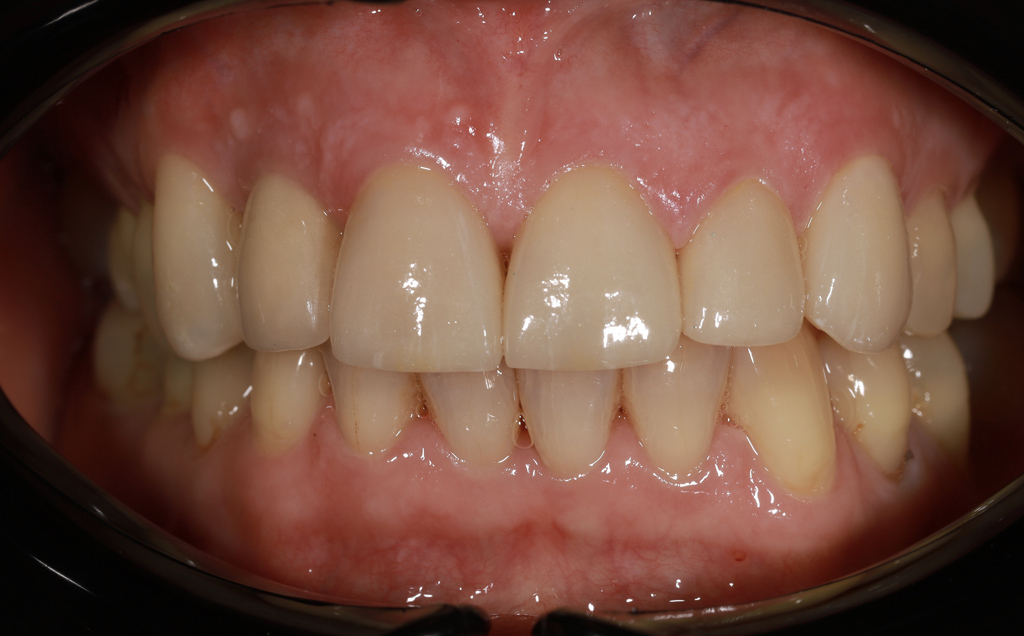

Zaprezentujemy serię poruszających historii pacjentów, którzy zdecydowali się na kompleksowe leczenie dentystyczne. Od przypadków zaawansowanej próchnicy, przez wypadki, które wymagały rekonstrukcji zębów, po pacjentów marzących o hollywoodzkim uśmiechu dzięki zastosowaniu licówek – każda historia jest dowodem na to, jak nowoczesna stomatologia może odmienić życie.

Skupimy się na innowacyjnych technologiach i metodach leczenia stosowanych w naszej klinice, które sprawiają, że te metamorfozy są możliwe. Od cyfrowego projektowania uśmiechu (DSD), przez ortodoncję i implanty, po zaawansowaną chirurgię szczękowo-twarzową. Omówimy, jak te techniki pracują razem, aby osiągnąć najlepsze wyniki.